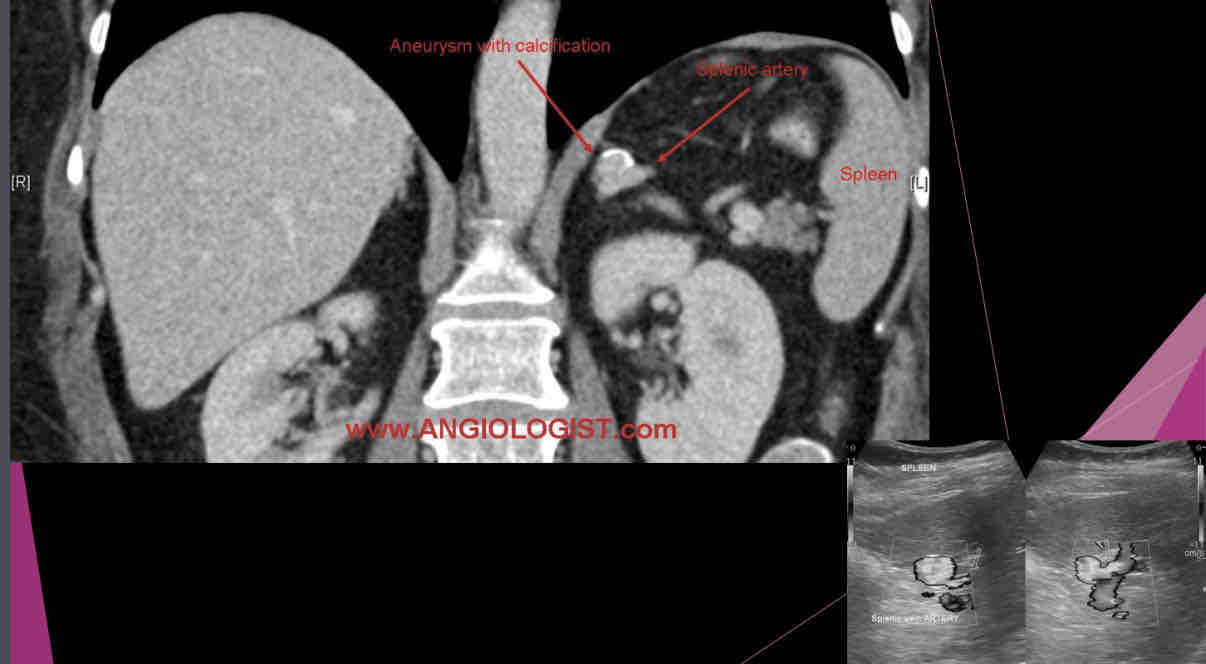

What describes the following?

•Those may be single or multiple and are most commonly involving the distal portion of the artery.

•Peripheral calcification is common, and mural thrombus may be present

•Usually, calcified circle seen in LUQ on X-ray and this is suspected

•Sonographically: may appear as cystic mass, or if calcified a hyperechoic shadow foci in area of artery

splenic artery aneurysm

Size of splenic artery aneurysms can range from…..